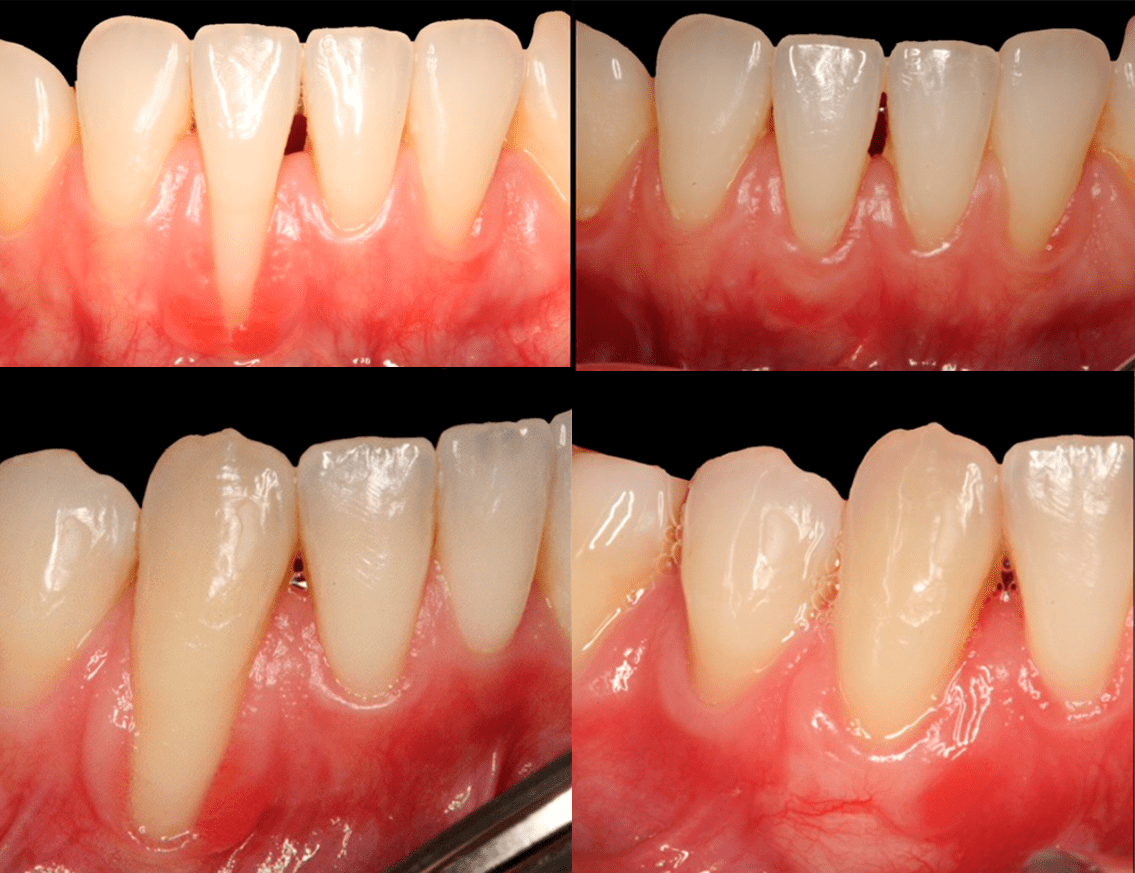

Caso clínico real: Injerto de encía antes y después en el sector anteroinferior

En este caso tratamos a un paciente con recesión gingival en la zona anteroinferior. Se realizó un injerto de tejido blando para recuperar la encía perdida y proteger las raíces expuestas.

En las imágenes puedes ver el antes y el después del procedimiento.